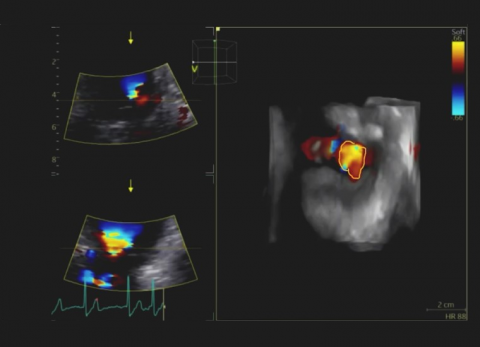

Wideo Echokardiografia. Przypadek 31

dr hab. n. med. prof. UJ Andrzej GackowskiPacjent z narastająca dusznością z podejrzeniem niedomykalności aortalnej.